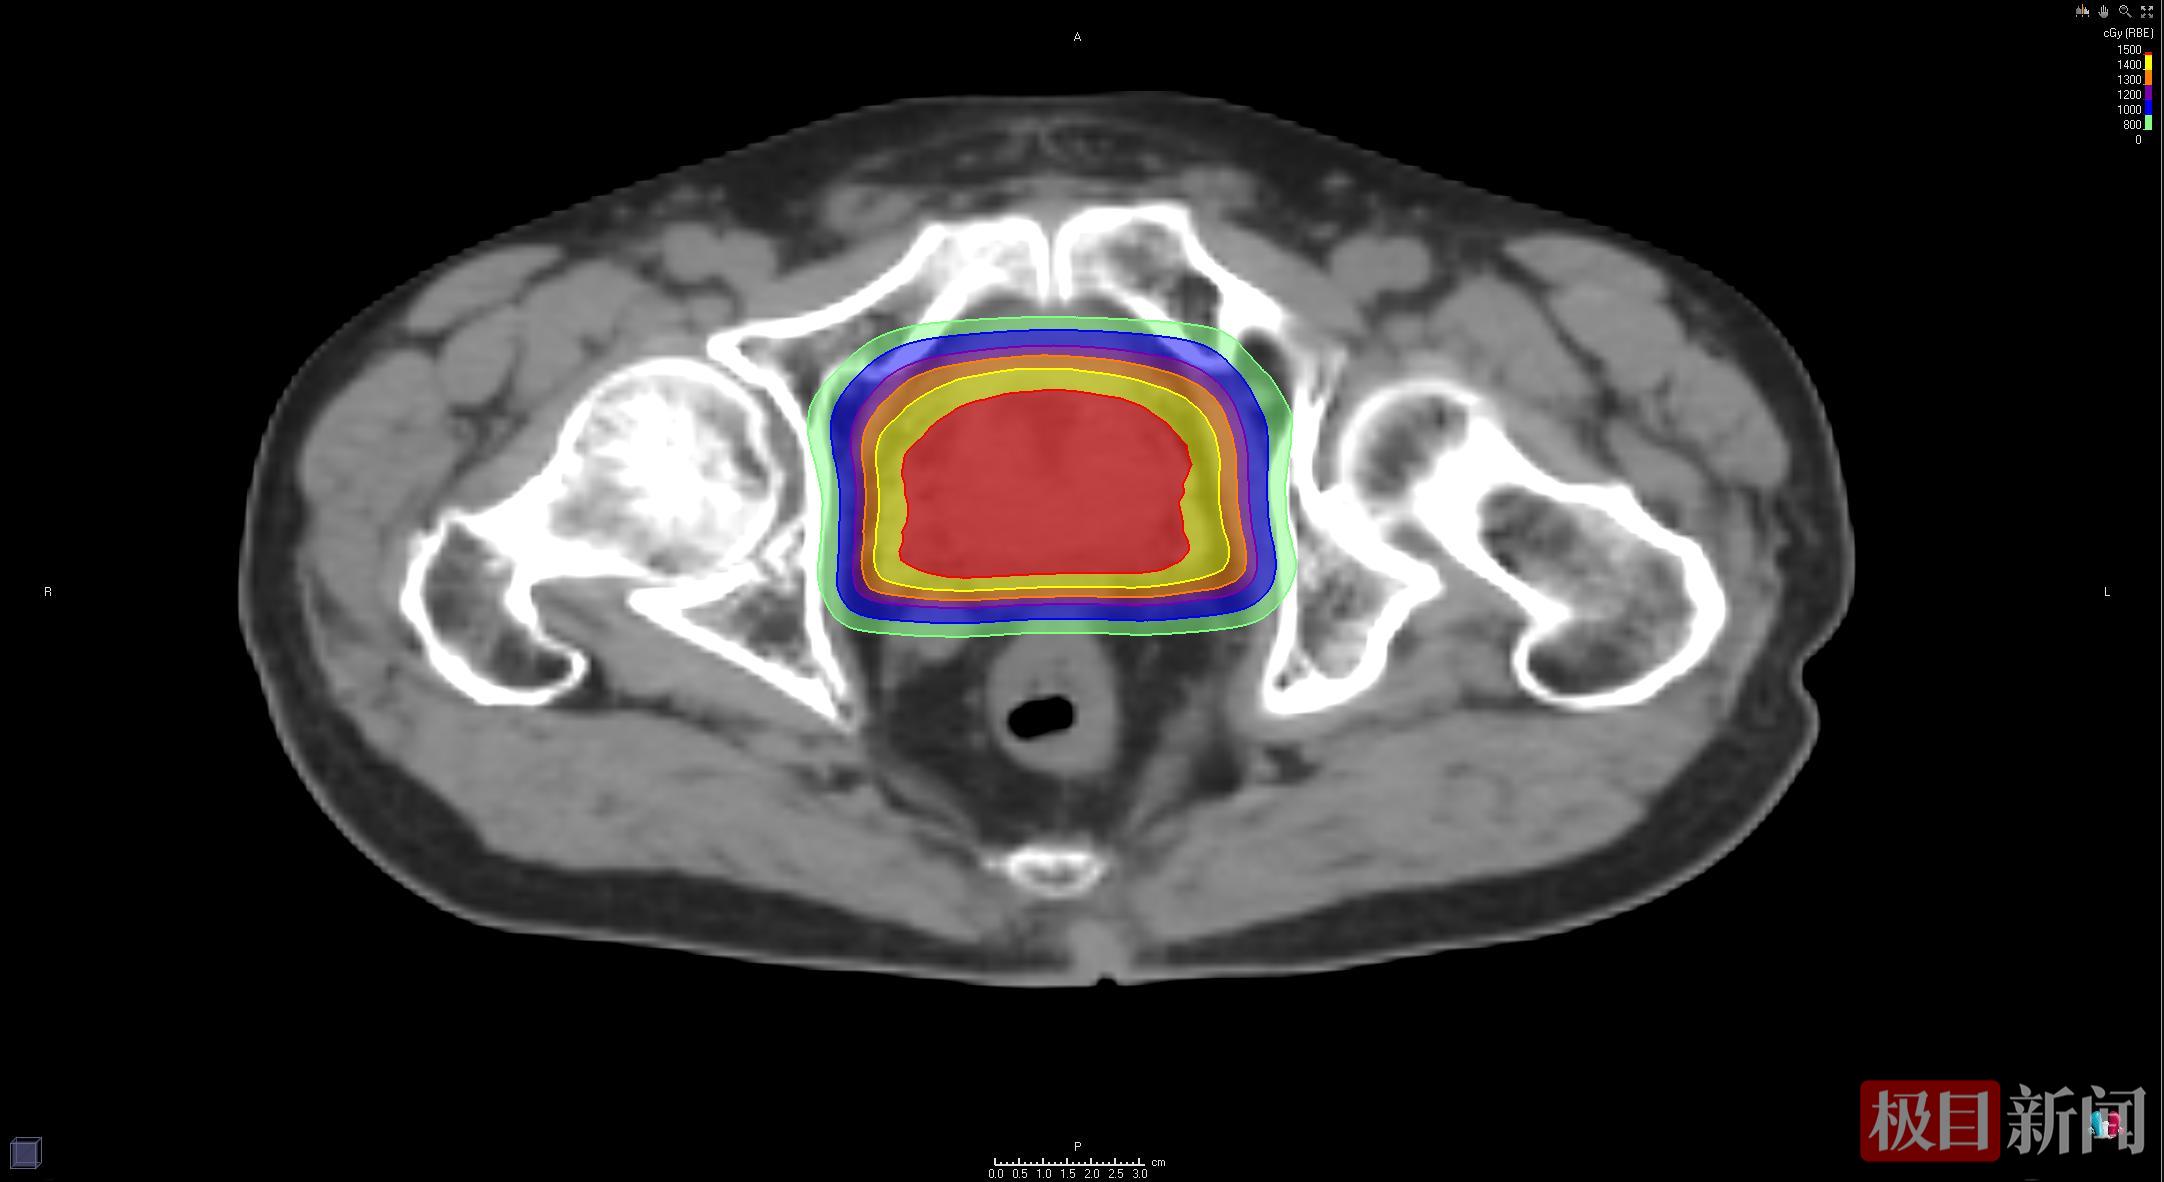

患者质子放疗靶区剂量分布图显示:直肠区域几乎无高剂量射线照射